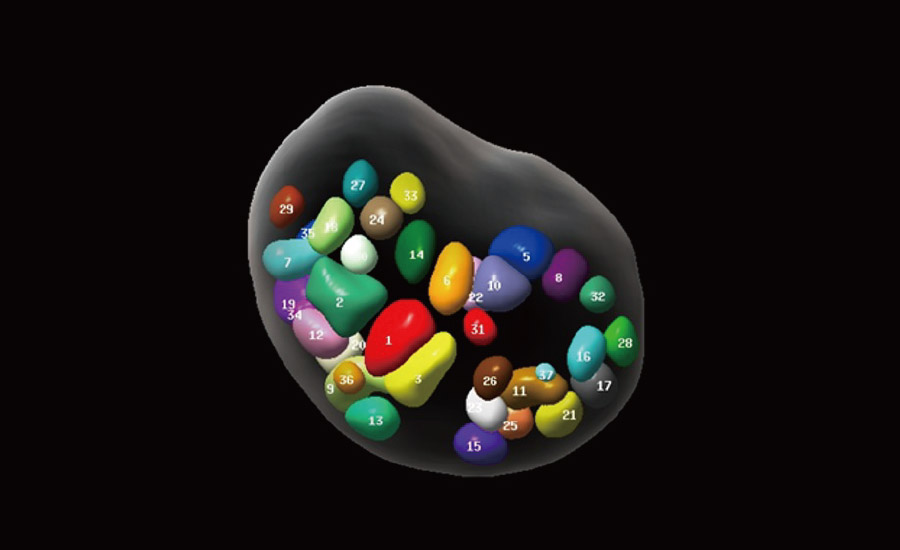

Fertilidade

Por meio da combina??o de algoritmos avan?ados e do conhecimento especĆfico da regi?o, a inovadora solu??o Smart Scene permite a identifica??o automĆ”tica das caracterĆsticas do tecido e fornece diagnĆ³stico especĆfico dos Ć³rg?os com informa??es completas. Com base na identifica??o automĆ”tica de cenĆ”rios, a solu??o realiza n?o apenas a varredura 2D inteligente com configura??es e medidas automĆ”ticas, mas tambĆ©m oferece informa??es 3D abrangentes em todas as etapas, desde a otimiza??o de imagens volumĆ©tricas atĆ© a difĆcil obten??o de planos 2D, e a quantifica??o durante todo o procedimento. Ele ajuda a reduzir em grande parte a dependĆŖncia de habilidades clĆnicas, ao mesmo tempo que aumenta a precis?o, a confian?a e a eficiĆŖncia no diagnĆ³stico.

Solu??es profissionais de ultrassom com informa??es abrangentes

- Protegendo novas vidas com solu??es em fertilidade e obstetrĆcia